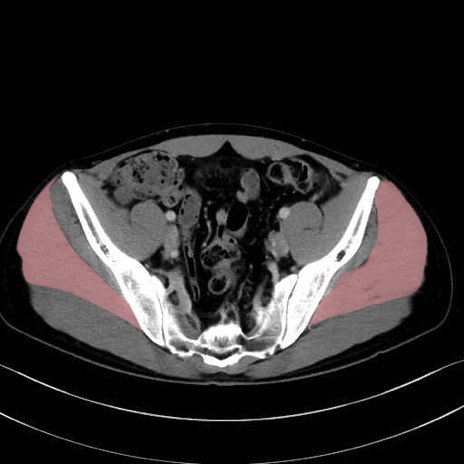

2. 腸腰筋群と骨盤底筋

大腰筋 (Psoas major)

腸骨筋 (Iliacus)